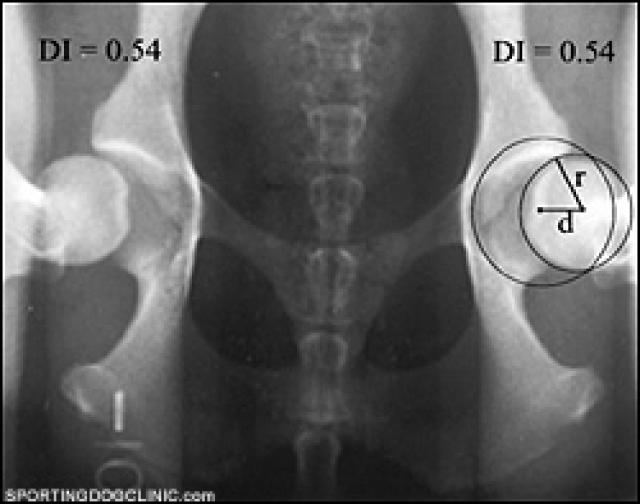

Hip dysplasia is a condition that occurs during the growth stage in dogs. It results in hip joints that don't fit together well and are looser than normal.